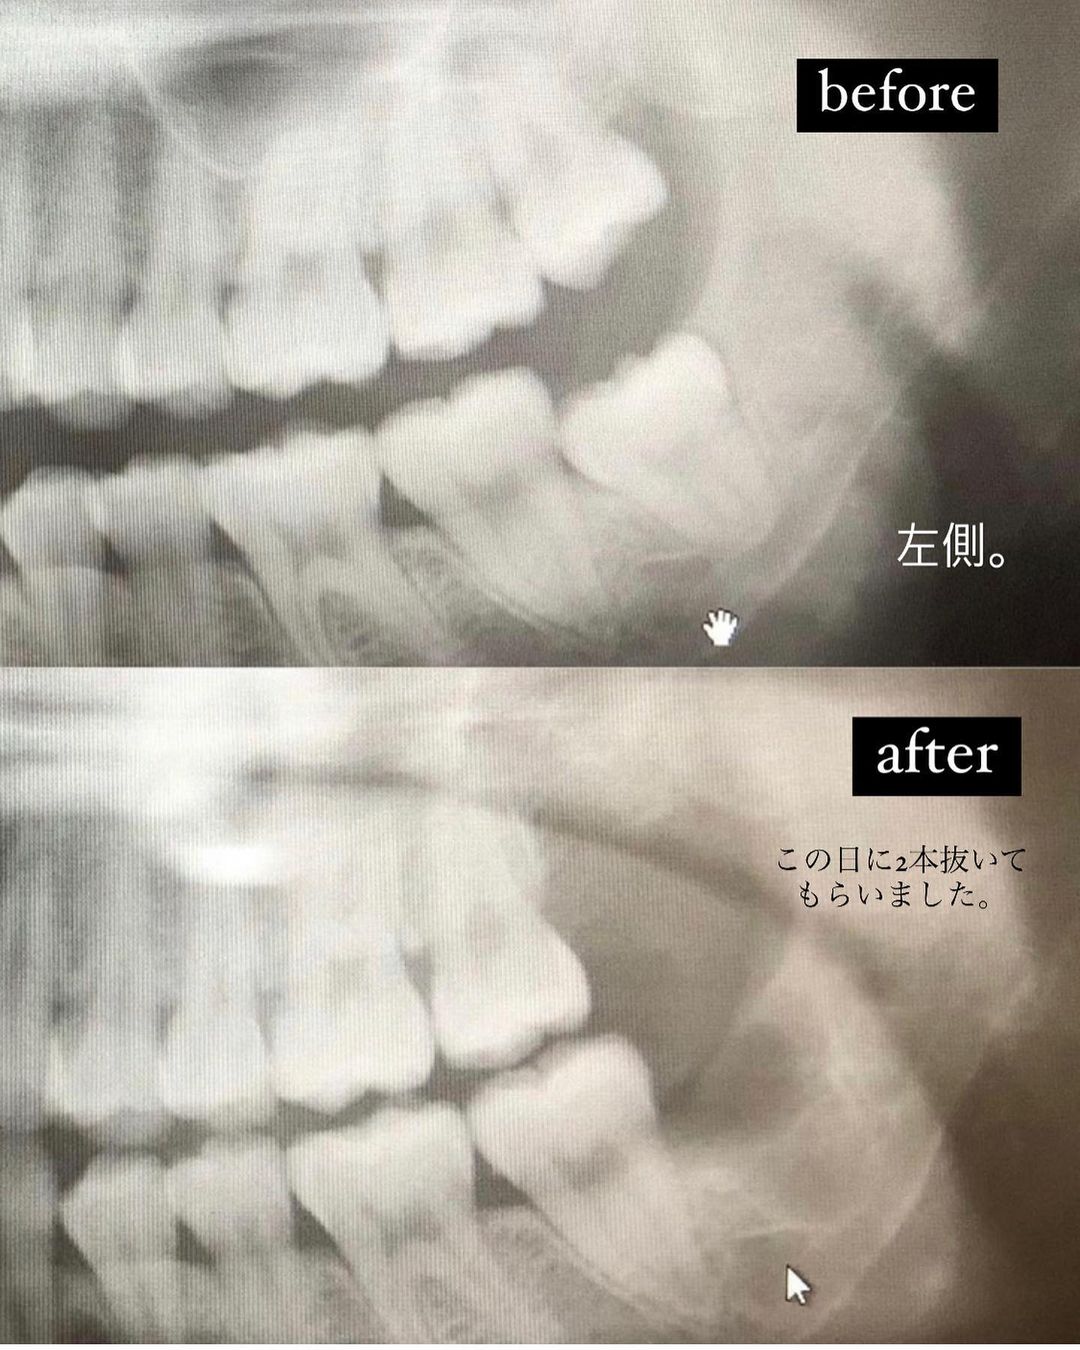

親知らずを4本ぬきました。

親知らずに対するコメントが多数寄せられていたので、今日はレポを詳しく載せます。長くなるので興味のある方だけみてみてください🦷

親知らずが原因で、炎症が何度か起きたため。これが地味に痛いし、腫れるし、中々やっかい。疲れているときにひょっこり現れる。🔥これが悪化すると虫歯の原因に…

横に倒れ、完全に埋まっていた右下の親知らずの抜歯のみ、腫れました。こちらは、歯茎を切ったり、骨を削ったり大工事だったため👷♂️半面ハムスターみたいになりましたが、私は一週間程度で、腫れはひきました。大事な予定がある方は、その辺りも考えて予約をするのがおすすめです。